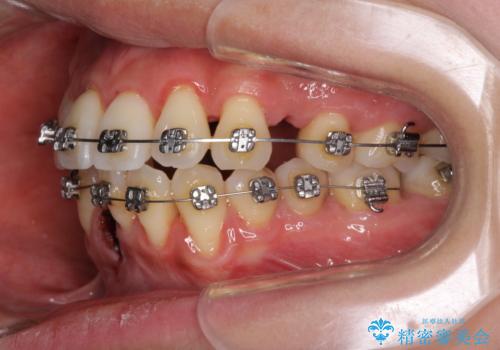

前歯のデコボコを治したい 費用を抑えた抜歯矯正

- 上下前歯のでこぼこを気にされ、矯正治療を希望された患者様です。

費用を抑えるため、メタルブラケットを採用し、抜歯矯正を行うこととしました。

通常であれば、上下顎左右小臼歯各1歯の合計4本を抜歯しますが、歯肉退縮の著しい下顎前歯を抜歯して欲しいという患者様の強い希望により、上顎のみ左右小臼歯2歯を、下顎は前歯を1歯を抜歯することとしました。

抜歯する歯を変更したため奥歯の咬合はアンバランスとなりましたが、前歯は綺麗に整い、歯肉退縮も回避できました。